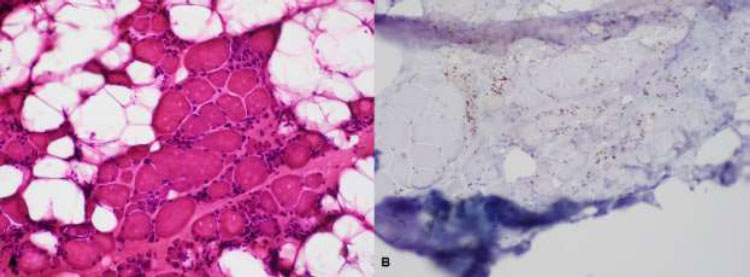

| Biceps brachii biopsy: Degenerating and necrotic fibers with macrophage invasion; few inflammatory mononuclear endomyseal infiltrates; no perifascicular atrophy nor perivascular and perimyseal inflammatory cells; no rimmed vacuoles; moderate increase in fibrous connective tissues. | Biceps brachii biopsy: Degenerating and necrotic fibers with macrophage invasion; few inflammatory mononuclear endomyseal infiltrates; no perifascicular atrophy nor perivascular and perimyseal inflammatory cells; no rimmed vacuoles; increased fibrous connective tissues and fatty replacement. |

The majority of NAM patients respond well to immunosuppressive treatment; however, they may continue to progress despite intense efforts because of muscle inflammation that cannot be sufficiently controlled [9]. Most anti-SRP serotype-positive patients are resistant to steroid therapy and require combination and further aggressive treatment, as they tend to have more systemic manifestations, including interstitial lung diseases (Figs. 1 and 2) [3,4].